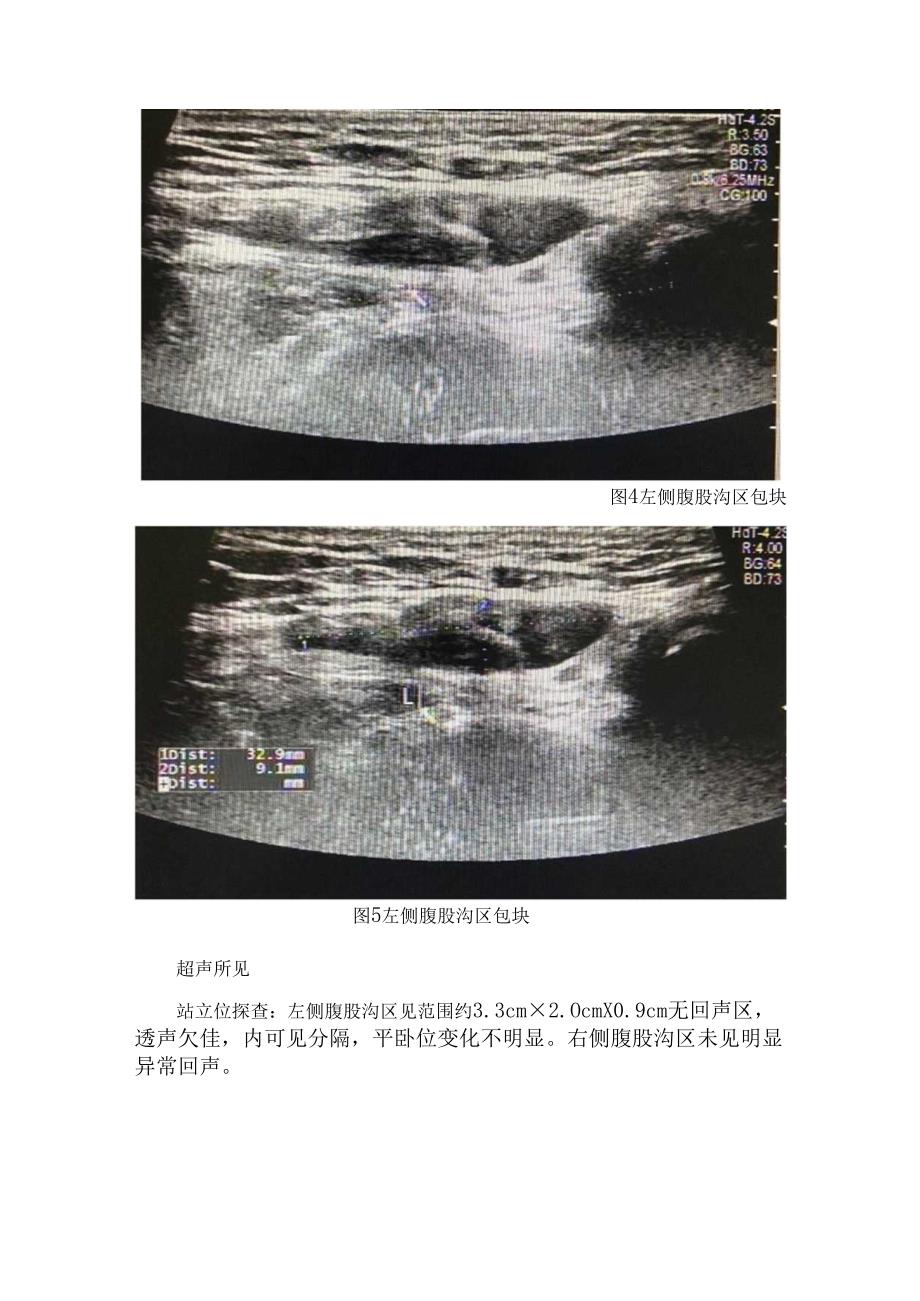

1、临床子宫圆韧带囊肿病例、病因、临床表现、超声表现、鉴别诊断及圆韧带子宫内膜异位症治疗要点子宫圆韧带囊肿图1左侧腹股沟区包块图2左侧腹股沟区包块左侧腹股沟区包块超声所见左侧腹股沟区见范围约4.4cm3.2cm2.Ocm无回声区,可见少量分隔,增减腹压大小无明显变化。右侧腹股沟区未见明显异常回声。超声提示左侧腹股沟无回声区,子宫圆韧带囊肿?积液?术后证实为左侧子宫圆韧带囊肿。图4左侧腹股沟区包块图5左侧腹股沟区包块超声所见站立位探查:左侧腹股沟区见范围约3.3cm2.OcmX0.9cm无回声区,透声欠佳,内可见分隔,平卧位变化不明显。右侧腹股沟区未见明显异常回声。超声提示左侧腹股沟无回声区,子宫圆

2、韧带囊肿?术后证实为左侧子宫圆韧带囊肿。Case 3图6左侧腹股沟区包块图7左侧腹股沟区包块8左侧腹股沟区包块超声所见左侧腹股沟区见范围约7.5cm4.7cm4.2cm无回声区,透声尚可,平卧位变化不明显。右侧腹股沟区未见明显异常回声。超声提示左侧腹股沟无回声区,子宫圆韧带囊肿?术后证实为左侧子宫圆韧带囊肿。子宫圆韧带囊肿合并腹股沟疝图9左侧腹股沟区包块超声所见左侧腹股沟区见范围约3.4cm2.6cm2.1cm无回声区,透声好,增减腹压未见明显变化。右侧腹股沟区未见明显异常回声。超声提示左侧腹股沟无回声区,子宫圆韧带囊肿?术后证实为左侧子宫圆韧带囊肿、左侧腹股沟直疝合并股疝。Case5图10左